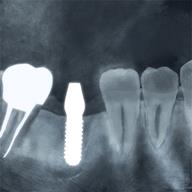

3つ目はインプラントです インプラントは歯のないところ、失ったところにチタン合金でできた人口の根を骨の中に埋めて土台とかぶせ物をしたものです。

当院ではCTを撮影してきていただきそれを元に画像診断を行います。実際そのシュミレーション画像は患者様にも見ていただき、お話を進めていきます。

画像診断を行ってからインプラントを行いますので正確な位置や方向を決定することができます。

当院では、インプラント治療術前の診査診断に、CT撮影とコンピュータ解析を行っています。

レントゲンやCT撮影を行い、顎の骨の量や厚み、神経や血管の位置を確認します。検査結果をもとに安全性に配慮した治療計画を立てます。